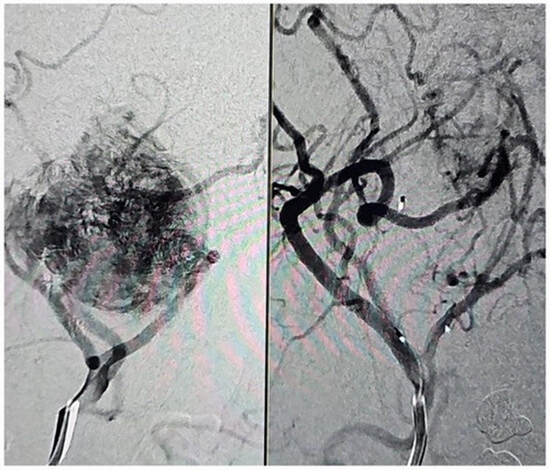

بررسی فراوانی و توصیف وضعیت بیماران به دنبال آمبولیزاسیون قبل از عمل در درمان پاراگانگلیومای کاروتید بادی؛ مطالعه ی case series کد خبر : 293218 کپی کلمات کلیدی آمبولیزاسیونپاراگانگلیوماکاروتید_بادی